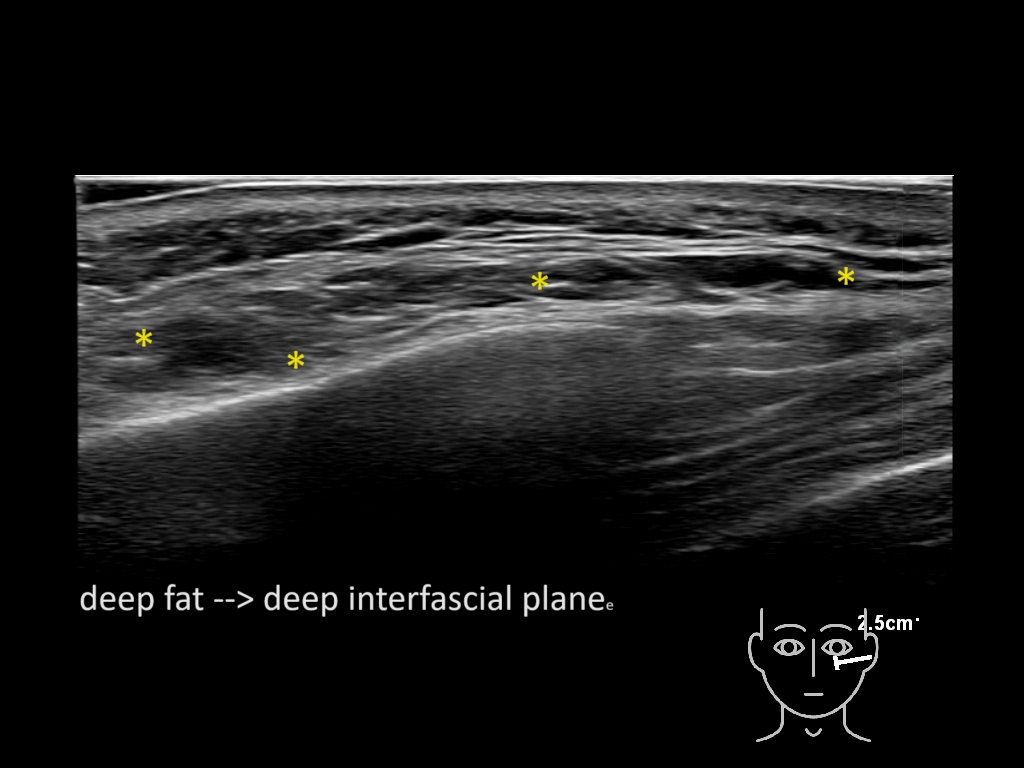

Filler behavior - Temple zygoma US

Study the first image to recognize the different layers. If you are sure about the layers, swipe to the second image to view the answer (if applicable).